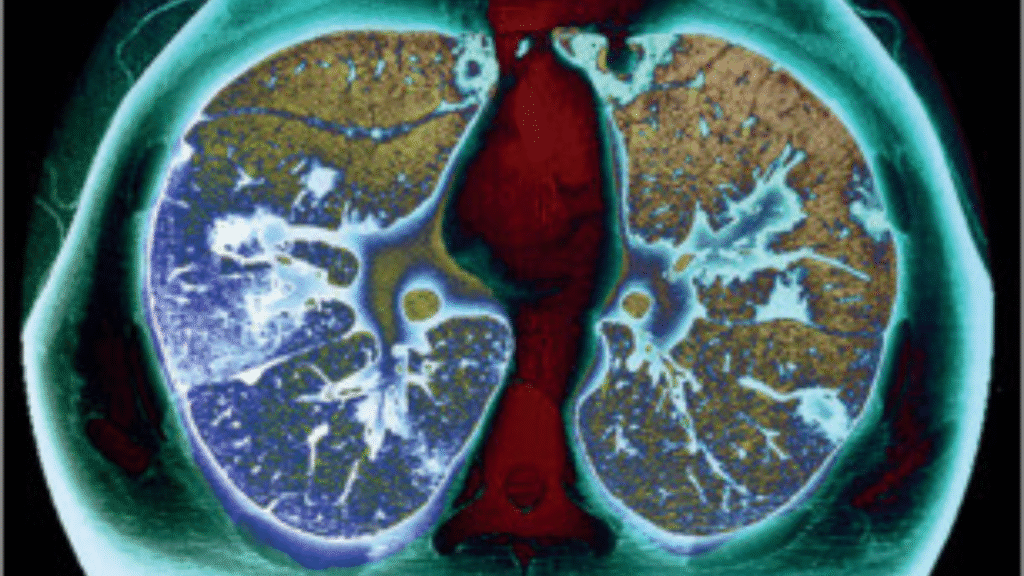

American Lung Association Calls for Expanded Insurance: Lung cancer remains the leading cause of cancer-related deaths in the United States, with tens of thousands of lives lost each year due to late-stage diagnoses. Recognizing the life-saving potential of early detection, the American Lung Association (ALA) has renewed its call for expanded insurance coverage for lung cancer screening, urging both public and private insurers to broaden access to low-dose CT scans (LDCT). This proactive move seeks to reduce barriers for high-risk individuals who could greatly benefit from early and accurate diagnosis.

The American Lung Association emphasizes that expanding insurance coverage can significantly enhance public health outcomes. Currently, lung cancer screening is recommended annually for adults aged 50 to 80 who have a significant smoking history, yet a large number of eligible individuals remain uninsured or face out-of-pocket expenses that discourage timely screenings. The ALA is pushing for comprehensive insurance reform to ensure that lung cancer screening is treated as an essential preventive service, much like mammograms or colonoscopies, with minimal to no cost for the patient.